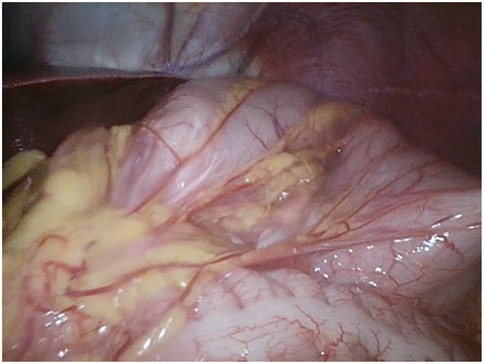

Background Acute gastric volvulus is a rare condition in children, and a delay in diagnosis may lead to gastric ischemia, perforation and even death. It is sometimes associated with wandering spleen, a condition where the spleen migrates from its normal anatomical position due to the absence of fixation ligaments. We report the first case of a patient affected by Pitt-Hopkins syndrome with simultaneous acute gastric volvulus and wandering spleen. Case report A 6-year-old male affected by Pitt-Hopkins syndrome, was urgently referred for acute abdominal pain and 24-hour history of non-bilious and non-bloody emesis. X-ray showed a massive gastric dilatation. Upper gastrointestinal series (UGI) revealed a gastric outlet obstruction. An emergency laparoscopy revealed a gastric mesoaxial volvulus with hypotonic wall with no sign of ischemia or perforation associated with a wondering spleen. Gastropexy was performed by anchoring the gastric greater curvature to the anterior abdominal wall covering the spleen in a good position in the left upper abdomen, completely covered by the gastric fundus. The patient made uneventful recovery and was completely asymptomatic. Conclusion To our knowledge, this is the first case of simultaneous gastric volvulus and wandering spleen in a patient affected by Pitt-Hopkins syndrome. Laparoscopic gastropexy is an easy procedure and combines the advantages of all surgical techniques adopted in previous eras.